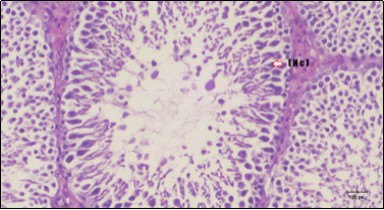

Histological examination of pancreas of the control rats showed normal sized islets of pancreas (Ip) compared to the diabetic rats which showed markedly atrophic islets of pancreas (I.p.) (Figure 8 and Figure 9). Pancreas of in groups (3) and (4) rats showed mild atrophic islets of pancreas (I.p.) with inflammatory cellular infiltrate (Figure 10 and Figure 11). The pancreas of rats in group (5) showed nearly normal islets of pancreas (I.p.) with few inflammatory cellular infiltrate (I.c.) (Figure 12).

Figure 12.Photomicrogragh of pancreas section of treated rat with both Fenugreek and Glimepiride showing nearly normal islets of Langerhans with spindle (arrow) & polygonal cells (dashed- arrow). (H&E) (40x).

Photomicrogragh of pancreas section of treated rat with both Fenugreek and Glimepiride showing nearly normal islets of Langerhans with spindle (arrow) & polygonal cells (dashed- arrow). (H&E) (40x).